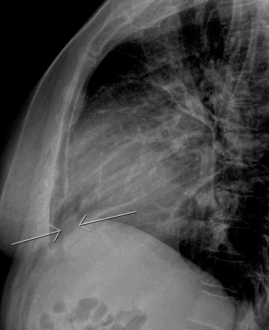

CXR of pericardial effusion: Above are images of pericardial effusion on chest X-ray. On the left, cardiomegaly with a slight water bottle appearance can be appreciated. In addition, a retrocardiac air-fluid level with the air lower than the fluid despite the upright position of the patient is indicative of a pericardial effusion. The fluid is contained within the pericardium and sitting atop some aerated lung, creating this reverse air-fluid level. On the right, the later film shows the “Oreo Cookie Sign” of a vertical opaque line between 2 radiolucent vertical lines indicative of pericardial fluid between the pericardial and epicardial fat. With large pericardial effusions, widening of the subcarinal angle may also be seen.